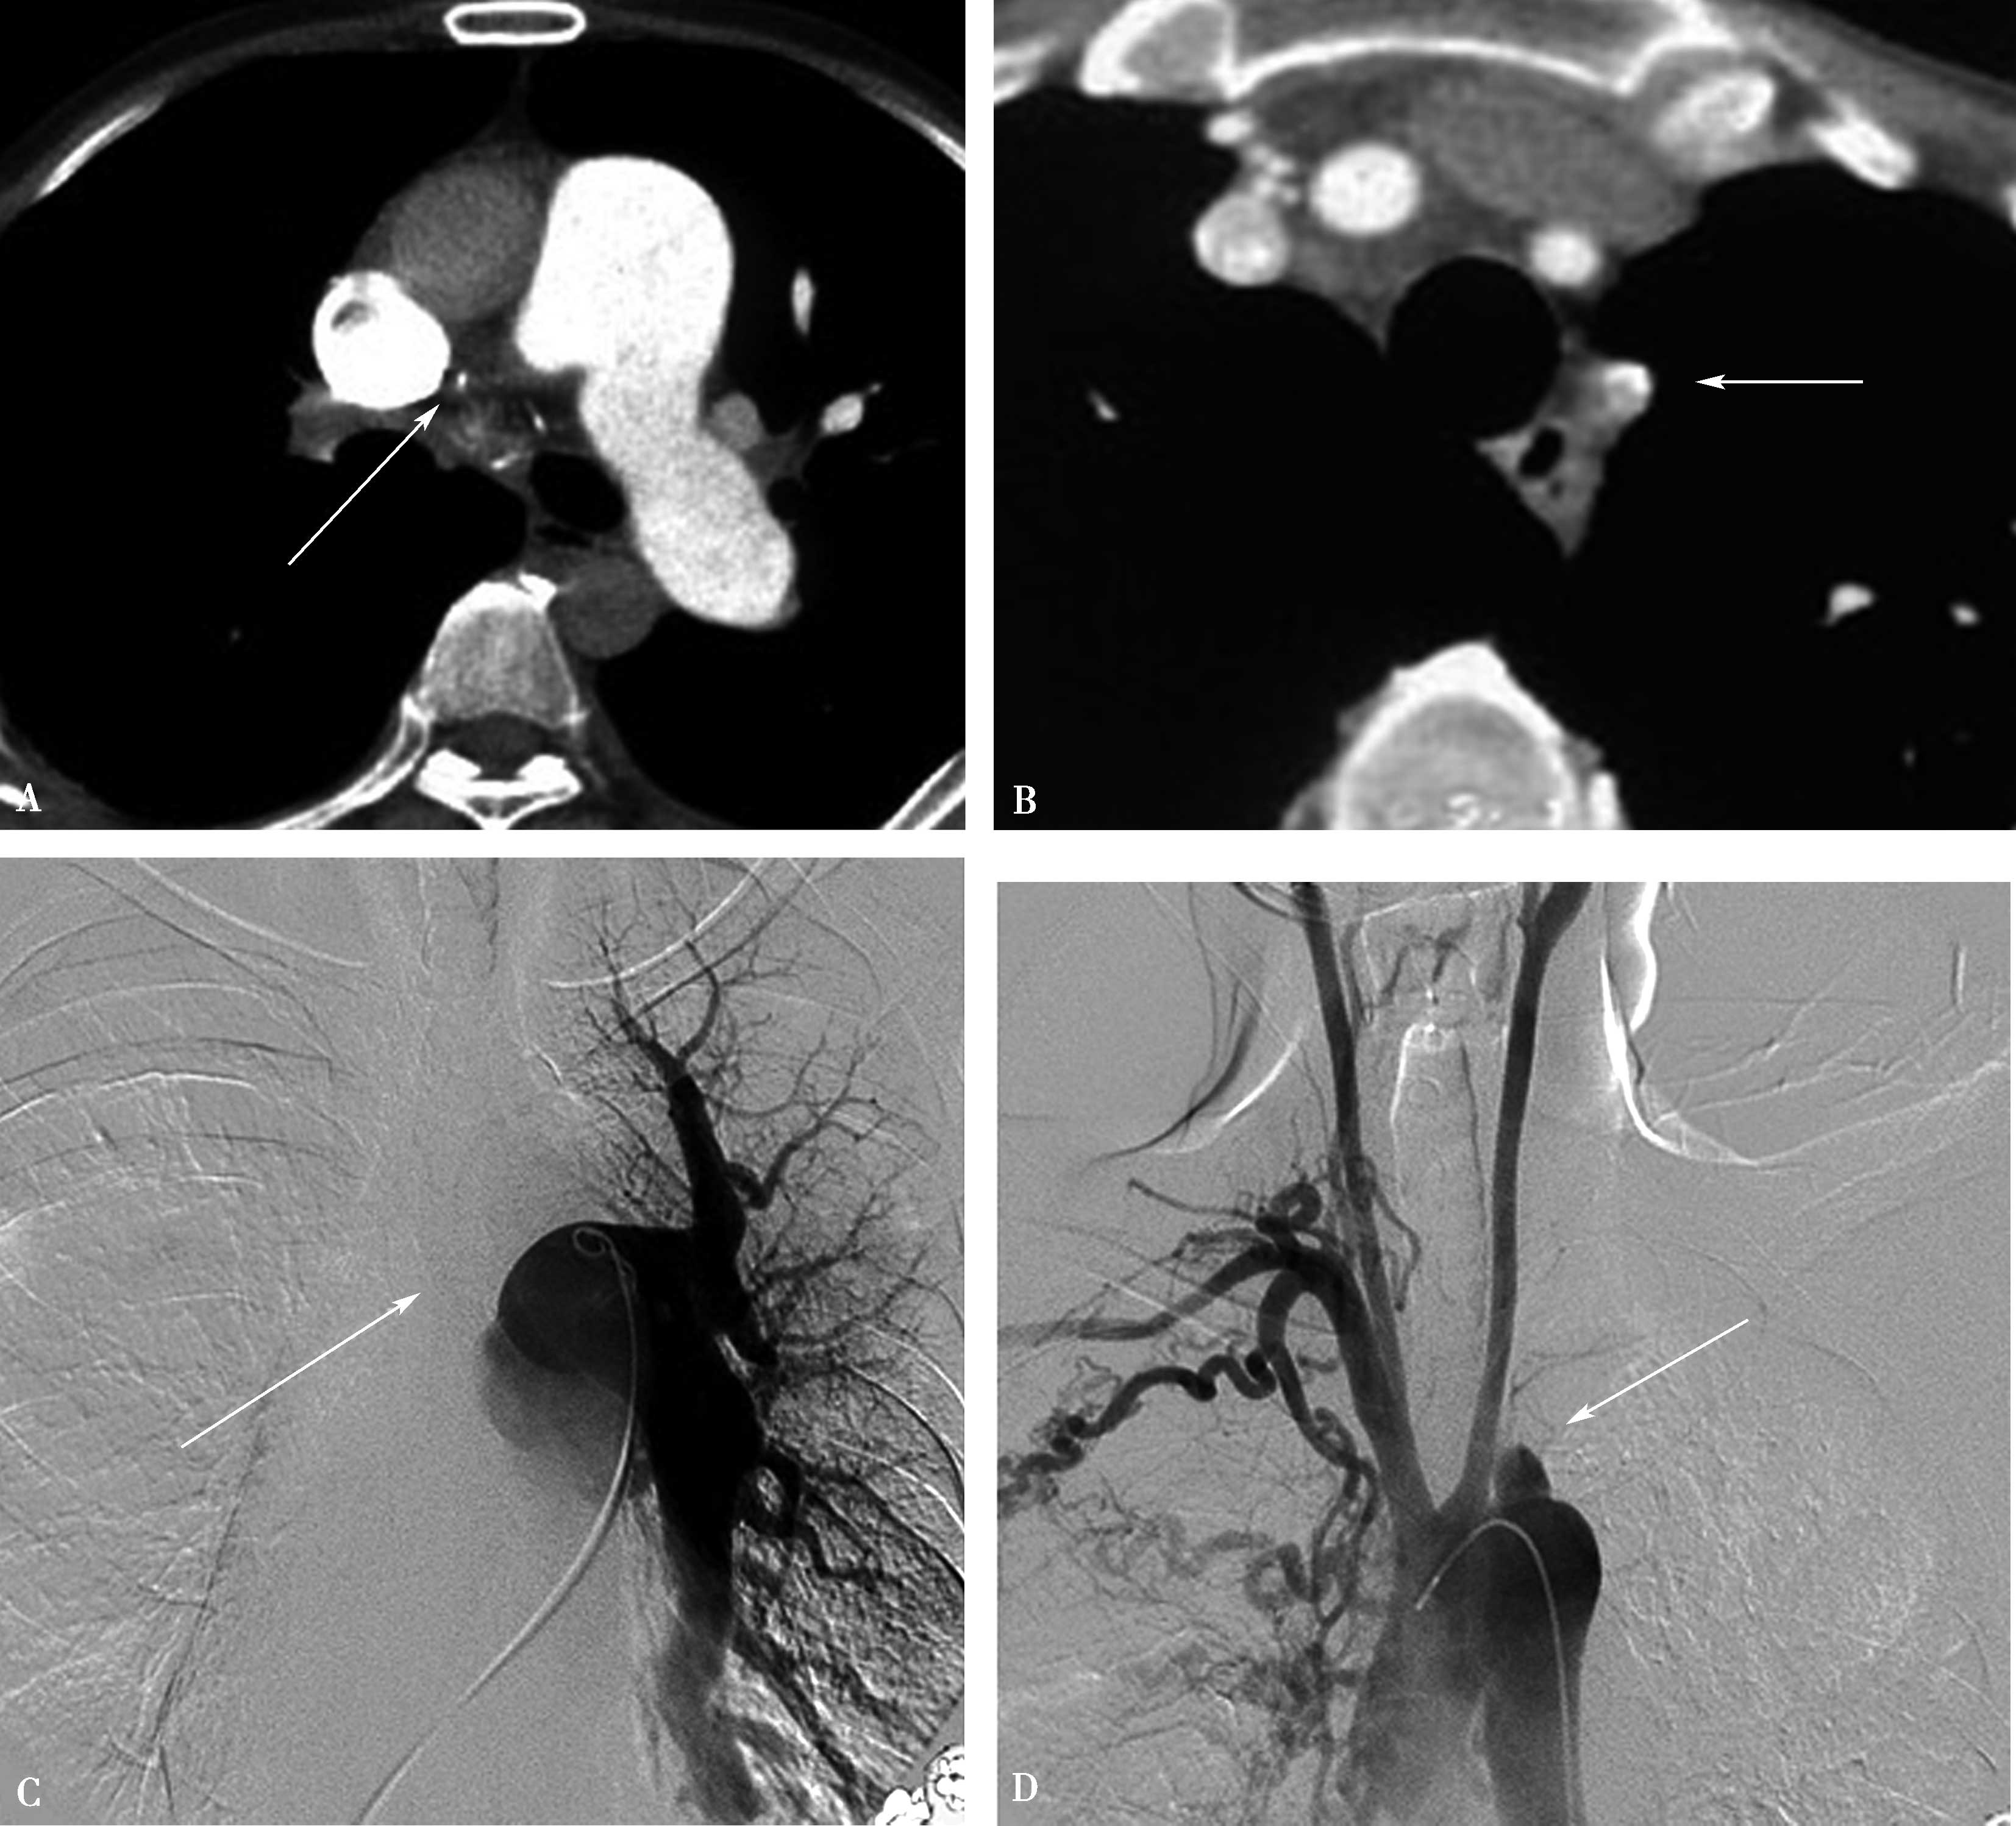

(二)双期扫描法(图8-1-5)

1.患者仰卧位,足先进,仰卧于检查床上。对检查范围以外的部位用铅衣、铅帽遮盖做好防护。

2.对比剂 对比剂浓度370mgI/ml,采用单筒高压注射器团注,流率为4.0~5.0ml/s,对比剂总量为70~90ml,如加做下肢静脉造影,可增加对比剂剂量为120~150ml。

3.扫描的范围 从肺尖到膈肌。

4.扫描采用的对比剂跟踪技术,监测层面设定在上腔静脉入右心房的层面,ROI定为上腔静脉,触发阈值定义为80~100HU。

5.当ROI的CT值达到阈值时启动增强扫描程序。实行双期扫描,第一期为肺动脉期,从肺尖扫描至膈肌,第二期为主动脉期,由膈肌扫描至肺尖,双期扫描范围一致。双期扫描的意义在于:①充分保证了对比剂团注时间与肺动脉CT数据采集时间的吻合;②肺动脉高压或/和右心功能不全循环时延长者,是一弥补措施;③多期观察可以辨别对比剂充盈不均造成的假象;④有利于对肺灌注的评价;⑤主动脉期可以兼顾观察左心系统的病变。

图8-1-5 CTPA两期扫描应用:患者,男,37岁,二尖瓣狭窄,肺循环高压,怀疑肺栓塞。第一期右肺下叶基底段对比剂充盈不充分(ABC↑);第二期充盈充分(DEF↑),排除肺栓塞诊断